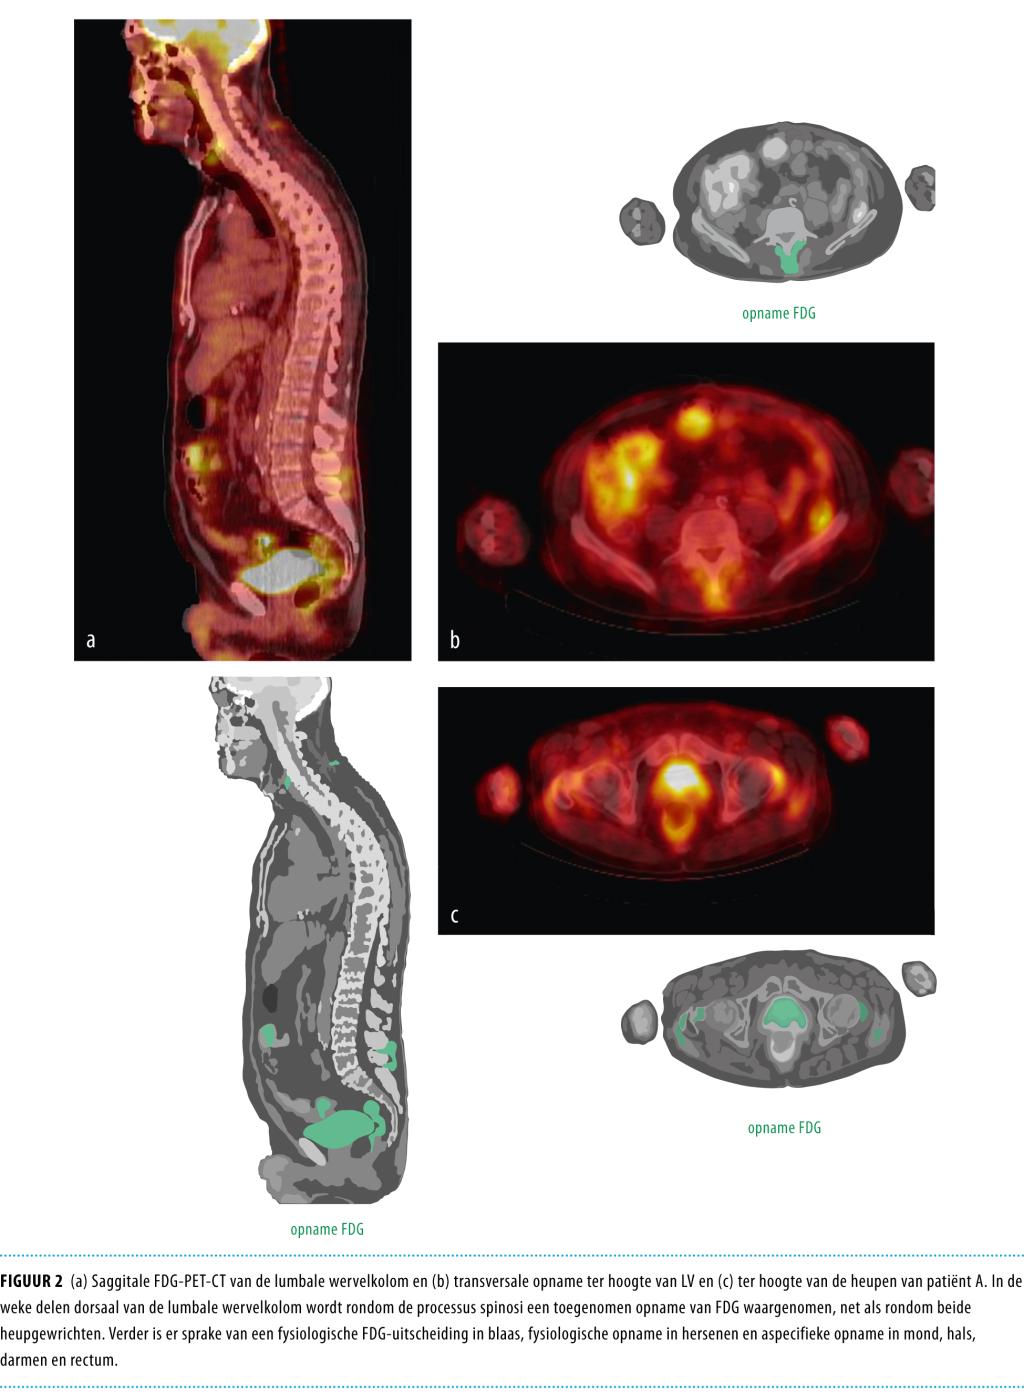

Een 64-jarige man werd opgenomen met toenemende lage rugpijn, uitstralend naar beide bovenbenen. Bij MRI van de wervelkolom werden inflammatoire afwijkingen gevonden bij wervels Liii-Lv, waarop patiënt 6 weken behandeld werd met flucloxacilline. De patiënt knapte echter niet op en de pijnklachten breidden zich uit. Ten slotte werden bij PET-CT afwijkingen gezien in schouders, rug en heupen, waarop de diagnose ‘polymyalgia rheumatica’ waarschijnlijk werd. Onder behandeling met prednison namen de pijnklachten snel af en 3 maanden later waren de inflammatoire afwijkingen bij MRI duidelijk afgenomen. Polymyalgia rheumatica (PMR) wordt vaak herkend aan het typisch klinisch beeld, maar bij atypische presentatie kan beeldvormend onderzoek hulp bieden. Meestal vindt men daarbij afwijkingen in het schouder- of het heupgewricht, maar ook cervicale en lumbale bursitis interspinosa kunnen passen bij PMR.